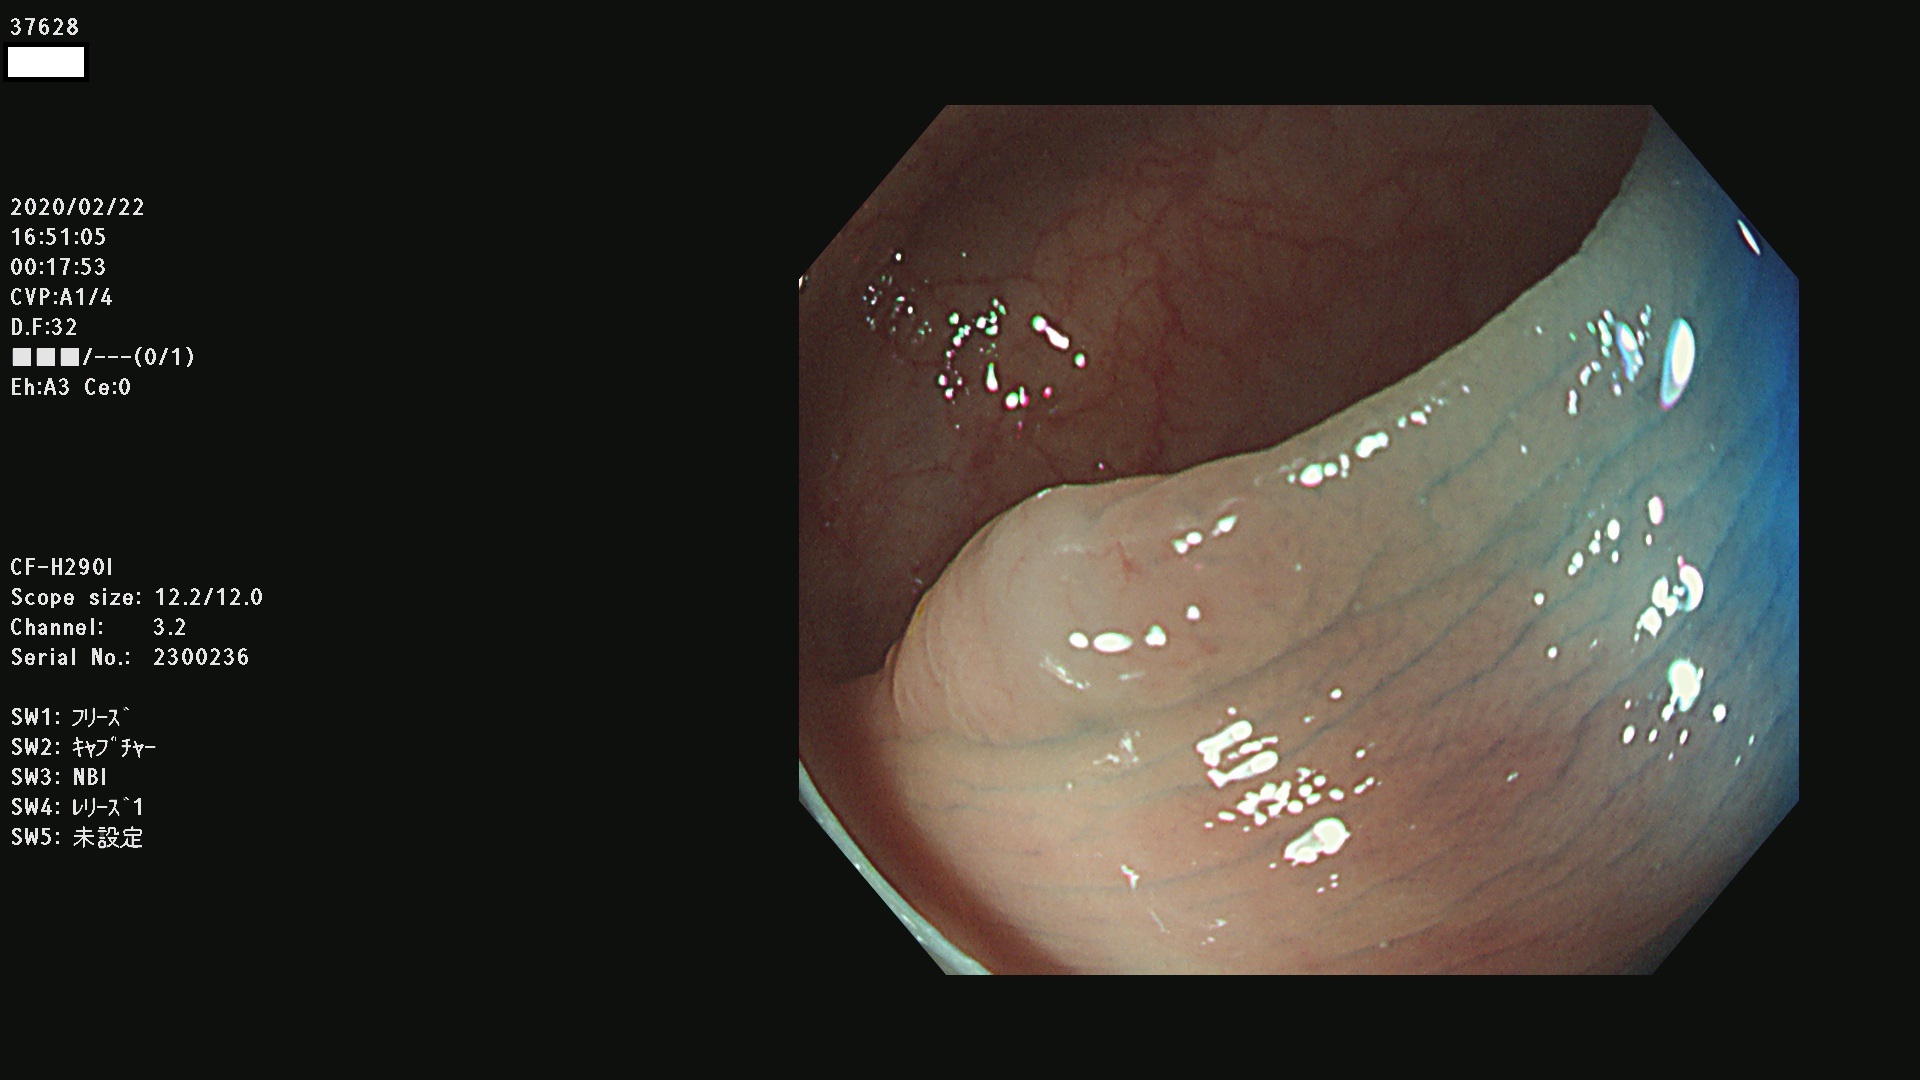

37600 37601 37602 37603 37604 37605 37606 37607 37608 37612 37614 37616 37618 37619 37620 37621 37622(SSAPのみ) 37623(SSAPのみ) 37624 37626 37627 37628 37629 37632 37633 37635 37636(SSAPのみ) 37639 37640 37641 37642 37643 37644 37647(SSAPのみ) 37648 37649 37650 37652 37653 37655 37657 37659 37660 37662 37664 37666 37668(SSAPのみ) 37670 37671 37672 37676 37677 37678 37679 37680 37682 37684 37685(SSAPのみ) 37686 37687 37688 37689 37690 37691 37692(SSAPのみ) 37693 37694 37695 37696 37697 37699

発見困難で危険性の高い平坦型病変(上記100名より抽出)